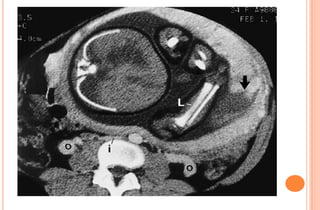

PHOTOS OF CT EVALUATION OF

PREGNANT WOMAN WITH TRAUMA– CT

SCANS DONE AS A PART OF INVESTIGATIONS

DONE IN EMERGENCY --- MATERNAL HEAD

AND ABDOMEN AS PER NEED OF INDIVIDUAL

CASE ---WITHOUT FEAR OF X RAYS

EXPOSURE TO FETUS IN UTERO

PHOTOS OF CTEVALUATION OF PREGNANT WOMAN WITH TRAUMA– CT SCANS DONE AS A PART OF INVESTIGATIONS DONE IN EMERGENCY --- MATERNAL HEAD AND ABDOMEN AS PER NEED OF INDIVIDUAL CASE ---WITHOUT FEAR OF X RAYS EXPOSURE TO FETUS IN UTERO